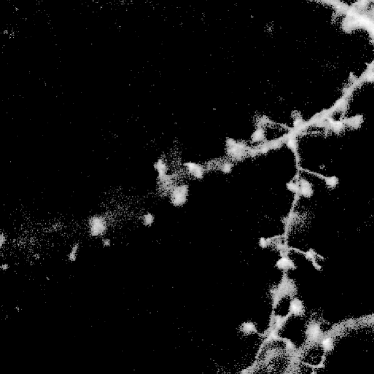

Finally, we applied our algorithm on a real confocal microscopy image of neurons. Fig. 4(a) depicts the observed image222Courtesy of the GIP Cycéron, Caen France. using the GFP fluorescent protein. Fig. 4(b) shows the restored image using our algorithm with the orthogonal wavelets. The images are shown in log-scale for visual purposes. We can notice that the background has been cleaned and some structures have reappeared. The spines are well restored and part of the dendritic tree is reconstructed, however some information can be lost (see tiny holes). This can be improved using more relevant transforms.

![]() |

| (a) | (b) |